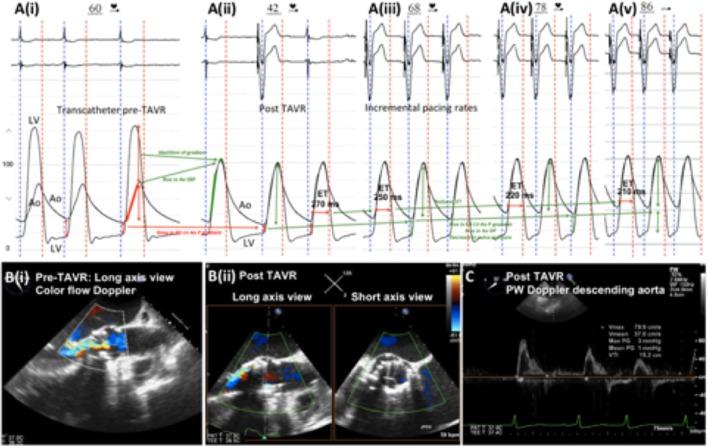

Transcatheter aortic valve replacement (TAVR) has become the preferred therapy for treatment of severe aortic stenosis in patients at intermediate to high risk of perioperative mortality following surgical aortic valve replacement. Haemodynamic assessment is an integral part of the procedure, and it is crucial for the operator to have an in-depth understanding of the haemodynamic alterations that occur during balloon aortic valvuloplasty and transcatheter valve deployment. Comprehension of the haemodynamic tracings is also pivotal for early recognition of periprocedural complications. With expanding indications for TAVR, it is imperative for members of the structural heart team to have an in-depth, nuanced understanding of transcatheter haemodynamic waveforms and their correlation with echocardiographic Doppler waveforms that are obtained periprocedurally during TAVR. This review provides a collection of transcatheter haemodynamic tracings and their corresponding Doppler echocardiography correlates that are demonstrative of physiological alterations and pathological lesions (complications) that occur during TAVR.